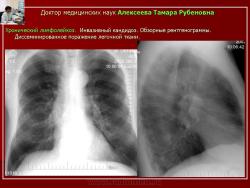

Рис.16. Б-ной С. Хронический лимфолейкоз. Инвазивный кандидоз.

Обзорные рентгенограммы. Диссеминированное поражение легочной ткани.

Рис. 17.Тот же б-ной С. Хронический лимфолейкоз. Инвазивный кандидоз.

Компьютерные томограммы. Диссеминированная форма инвазивного кандидоза. Множественные хаотично расположенные мелкие очаги уплотнения и более крупные с нечеткими контурами.